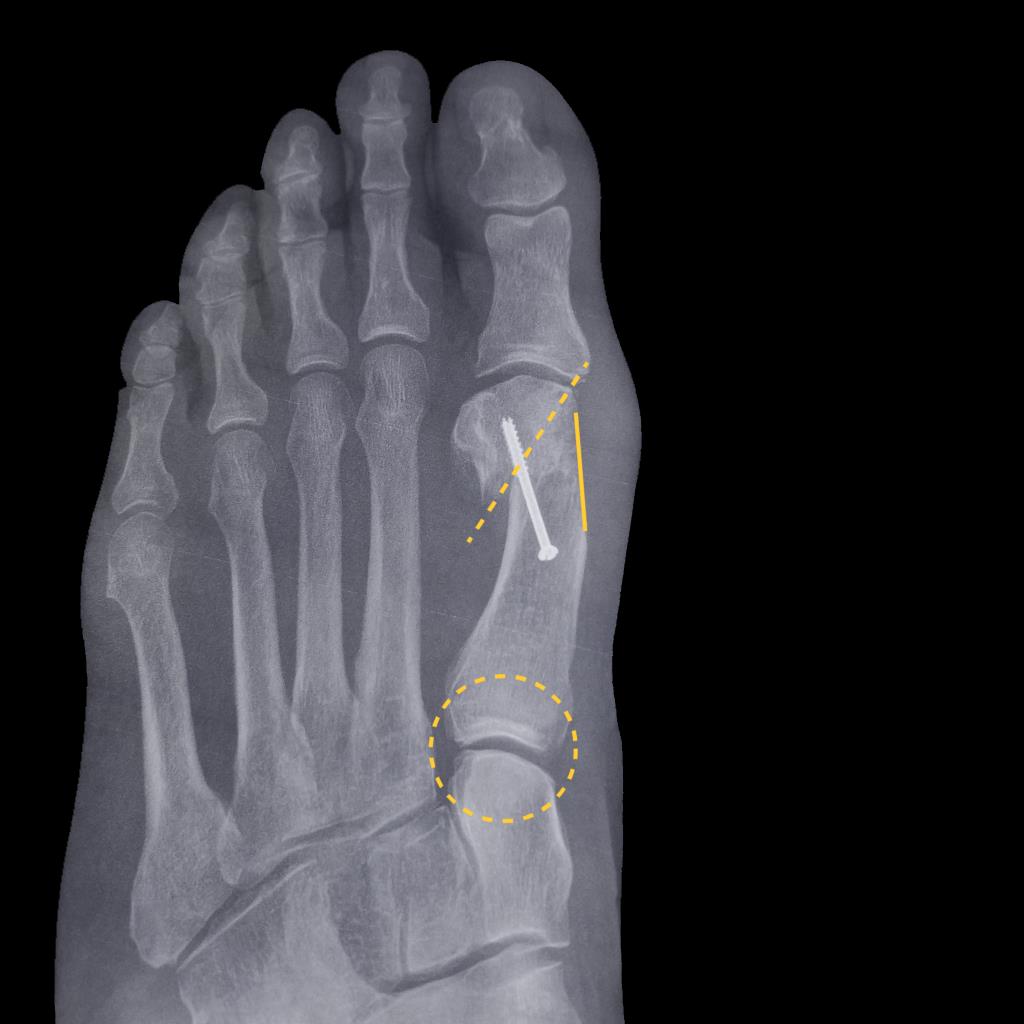

• Hallux valgus deformity commonly features an increased intermetatarsal angle between the first and second metatarsals, pronation of the first metatarsal around its longitudinal axis, and relative elevation or dorsiflexion of the first ray, with the sesamoid complex drifting lateral to the crista.

• Correcting at the first tarsometatarsal joint allows reduction of the intermetatarsal angle, restoration of sesamoid position under the metatarsal head, and re-establishment of a stable medial column, which can be more biomechanically advantageous than correcting only at the distal first metatarsal.

• Under-correction of first-metatarsal pronation can leave residual sesamoid malalignment and may predispose to recurrent deformity despite apparent correction on standard AP radiographs.